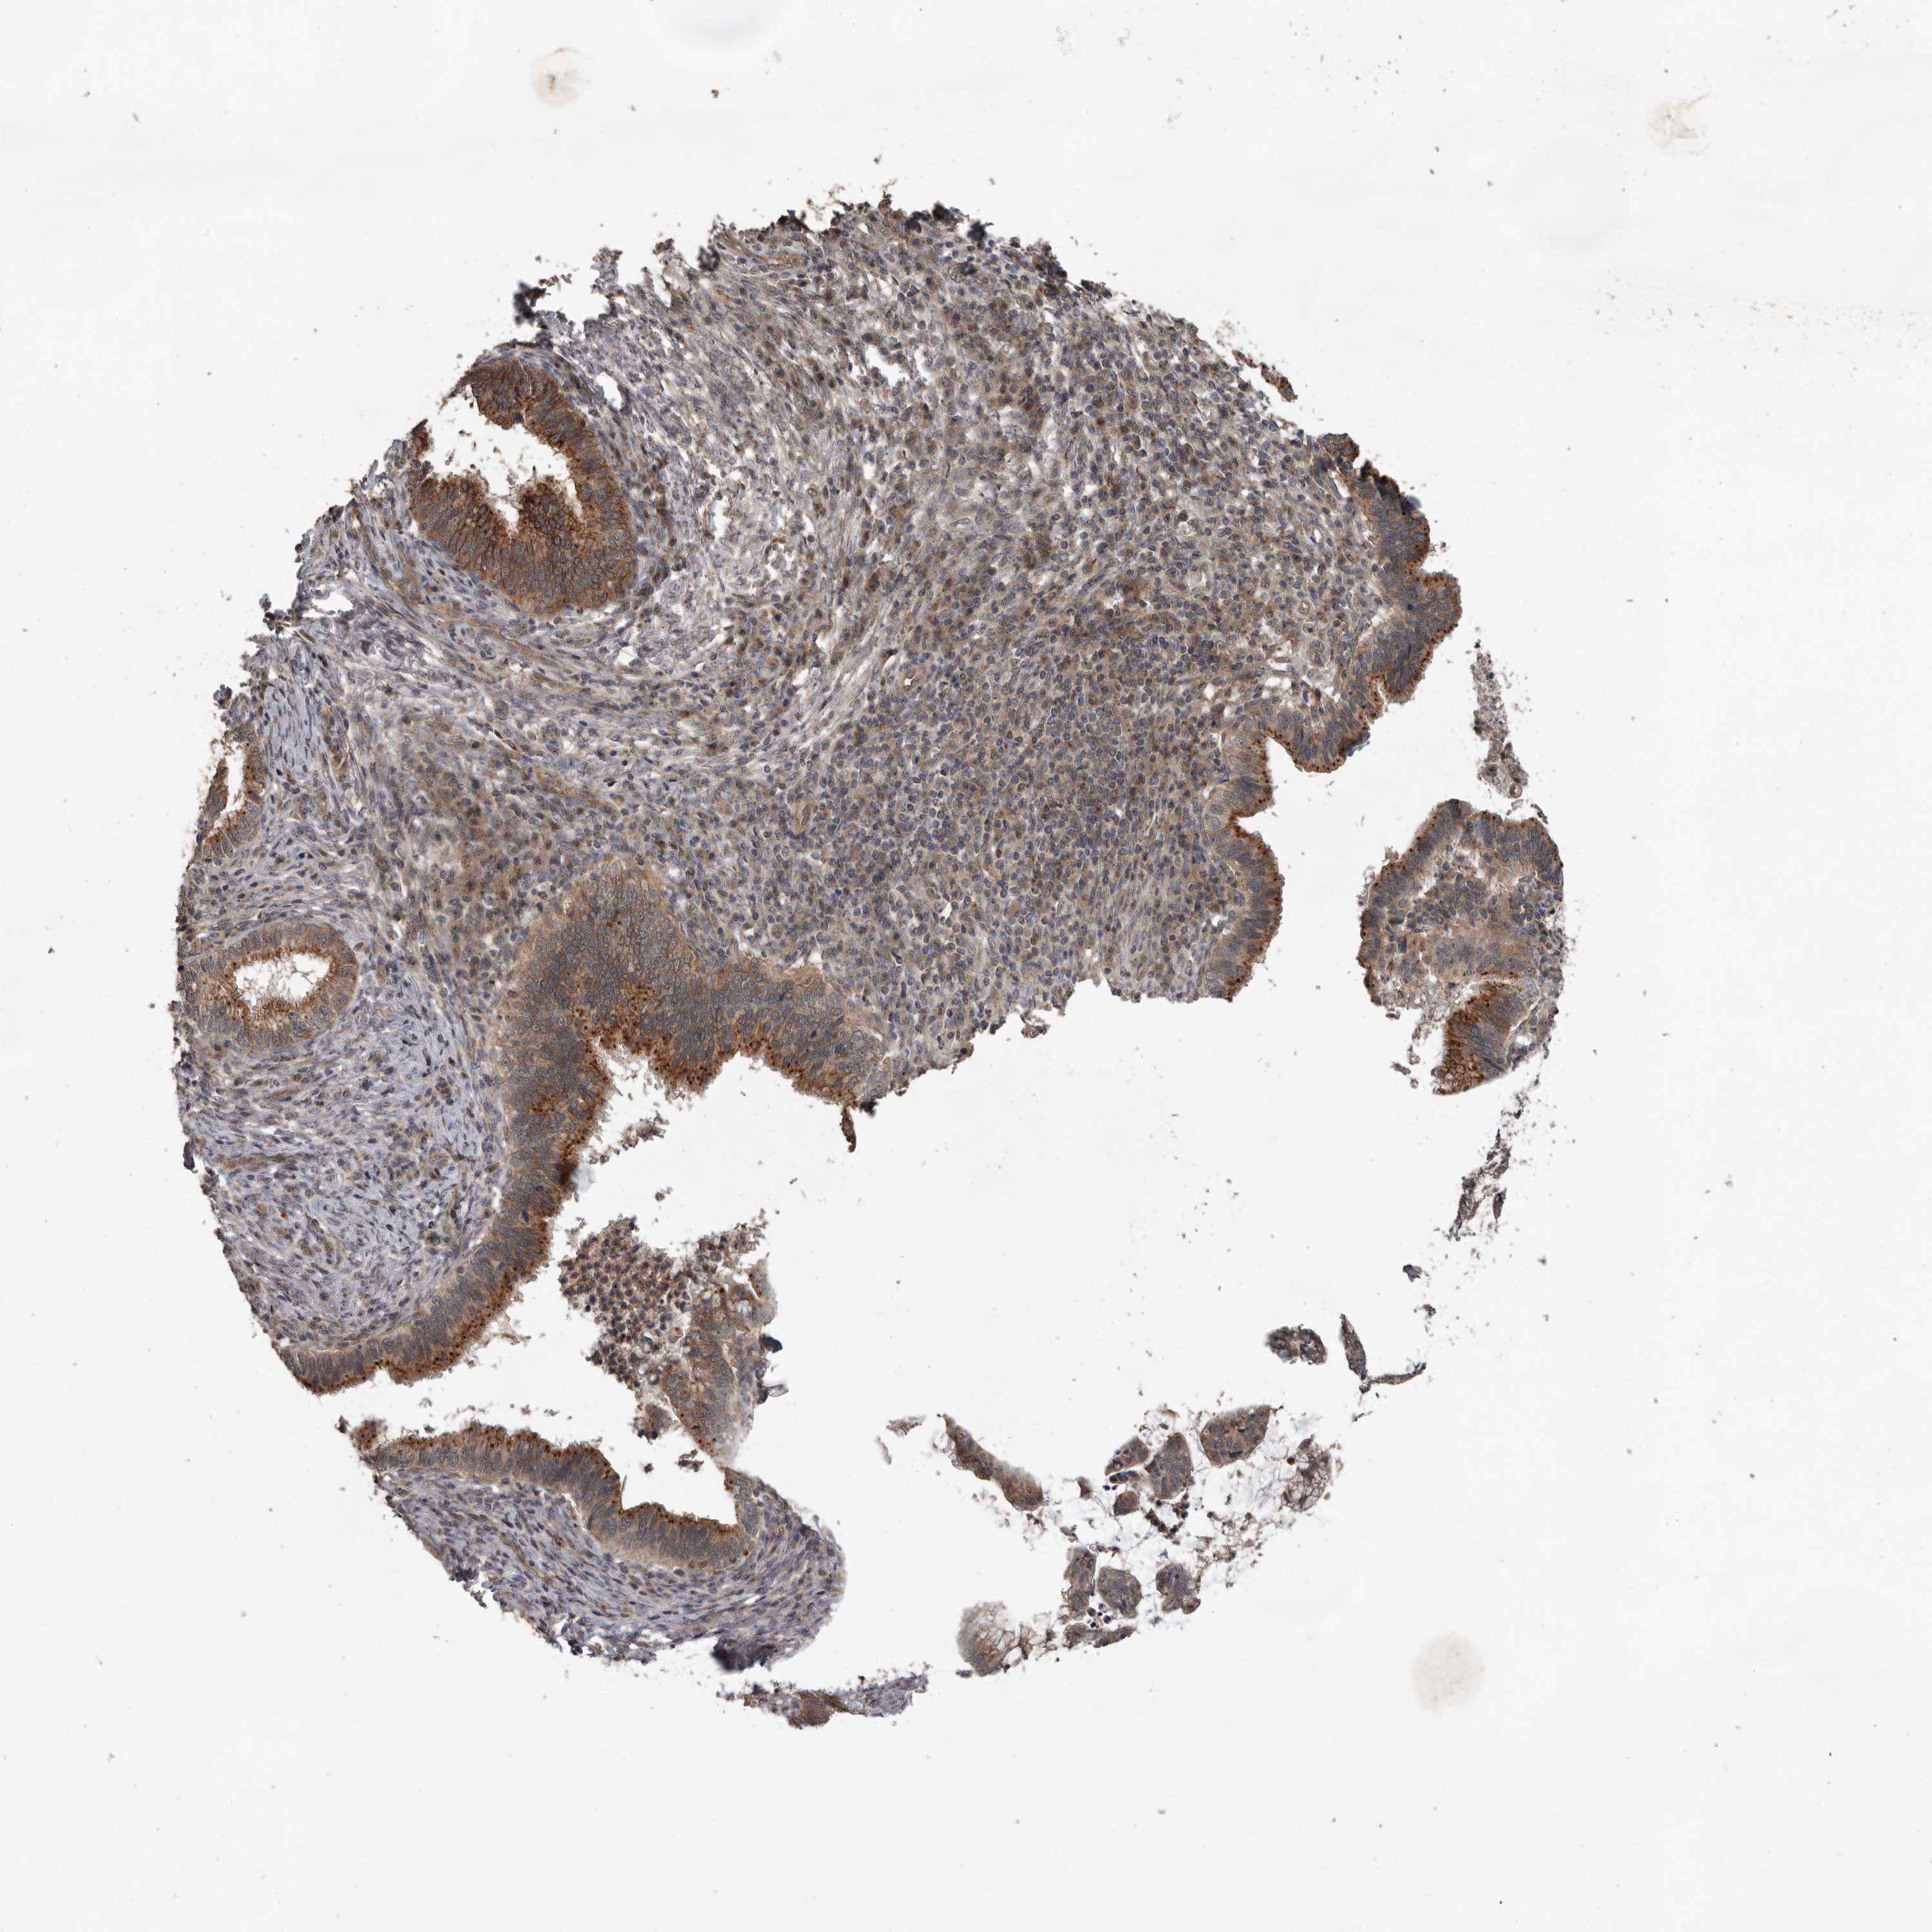

CERVICAL CANCER - Protein expressioni

A mouse-over function shows sample information and annotation data. Click on an image to view it in a full screen mode. Samples can be filtered based on level of antibody staining by selecting one or several of the following categories: high, medium, low and not detected. The assay and annotation is described here.

Note that samples used for immunohistochemistry by the Human Protein Atlas do not correspond to samples in the TCGA dataset.

Antibody stainingi

Antibody staining in the annotated cell types in the current human tissue is reported as not detected, low, medium, or high, based on conventional immunohistochemistry profiling in selected tissues. This score is based on the combination of the staining intensity and fraction of stained cells.

Each image is clickable and will lead to virtual microscopy that enables deeper exploration of all samples and also displays staining intensity scores, fraction scores and subcellular localization as well as patient and tissue information for each sample.

Antibody HPA028355

Antibody HPA028357

Staining

High

Medium

Low

Not detected

Intensity

Strong

Moderate

Weak

Negative

Quantity

>75%

75%-25%

<25%

None

Location

Nuclear

Cytoplasmic/membranous

Cytoplasmic/membranous,nuclear

Squamous cell carcinoma, NOS

Adenocarcinoma, NOS